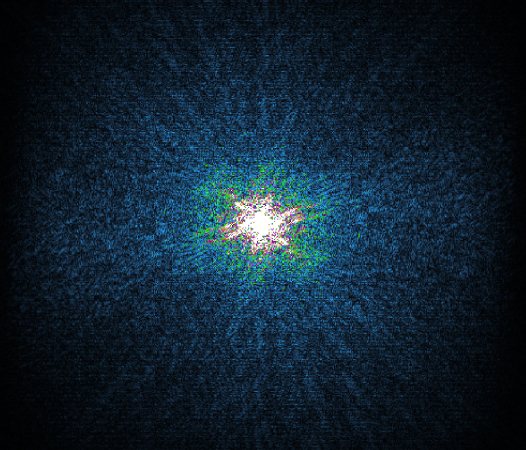

In the example below, only one fifth of the required MR radiofrequency signals is recorded. This results in a five times faster acquisition, with a subsampled k-space (top left) and inherent image artifacts after standard reconstruction (top right).

Basic compressed sensing principle